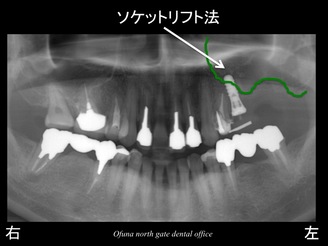

まだある程度骨が残っている手前の部分のみにソケットリフト法 を行い、インプラントを1本のみ埋入する計画です。

以下が手前の部分にインプラントを1本埋入した直後です。

このインプラントは、ソケットリフト法 を応用して埋入しました。